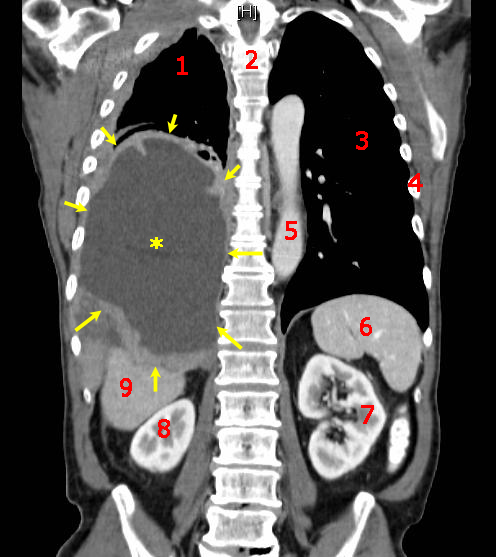

Mesothelioma is a malignant neoplasm of mesothelial cells.

Mesothelioma is strongly linked to occupational exposure to asbestos.

Mesothelioma presents with:

- Chest pain

- Dyspnea

- Recurrent pleural effusions